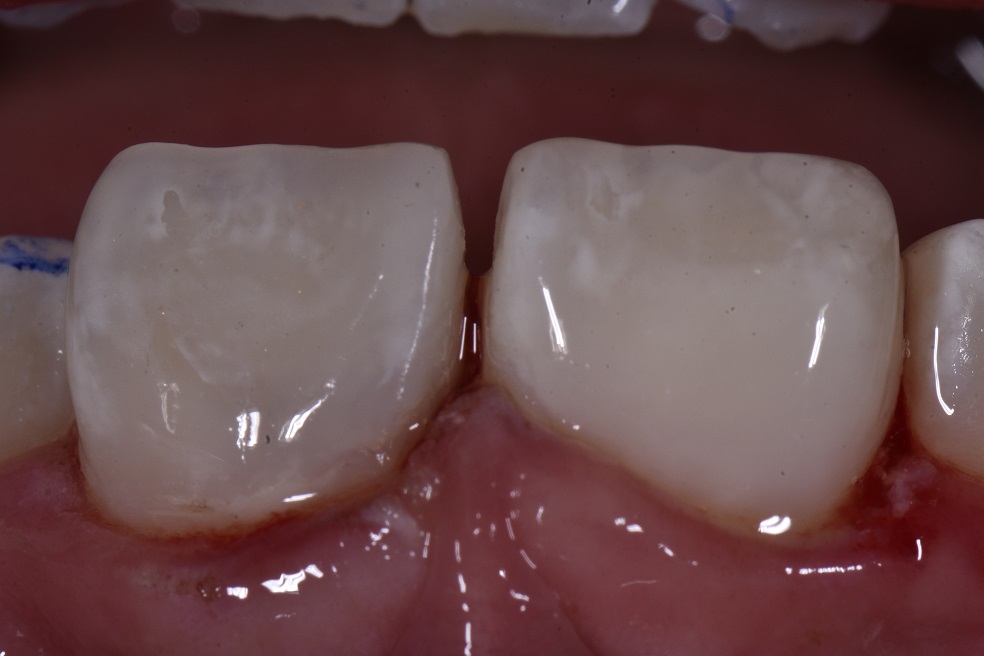

Huge Class IV fracture secondary to fracture on a 10 year old girl. Clear violation of biologic width, but parents wish to “see how she heals” before deciding on crown lengthening surgery. Laser diode gingivectomy (Biolase) set at 2.0W continuous.